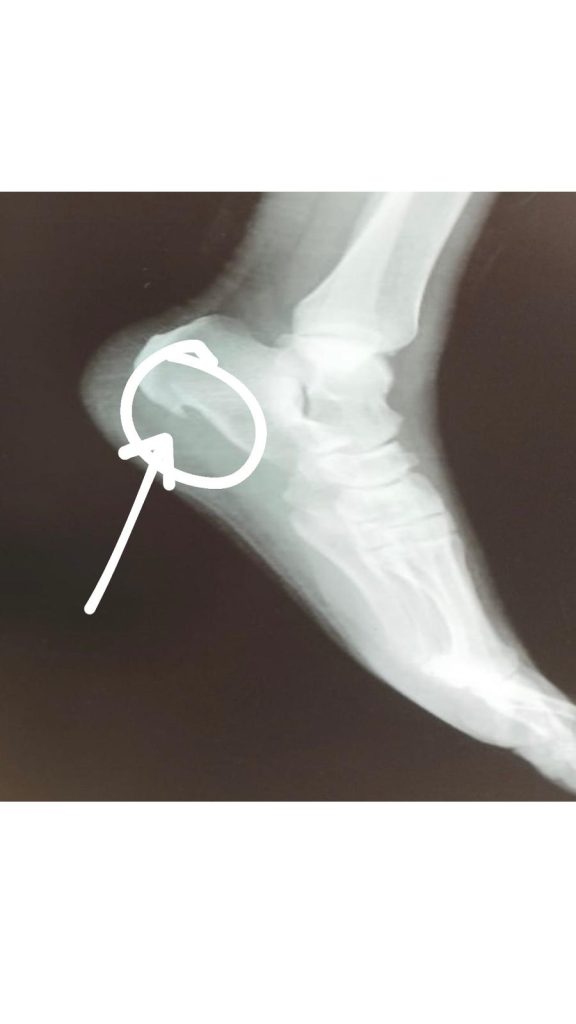

Es otra de las patologías que tratamos en la clínica muy a menudo. Suele estar relacionado con la fascitis plantar.

Procuramos redistribuir las cargas y eliminar la presión del punto doloroso, evitando el mecanismo lesivo. Todo ello, mediante el correcto estudio de la pisada, plantillas y si fuera necesario pruebas complementarias.